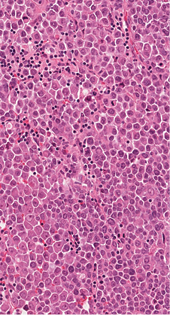

1 pav. Visą storosios žarnos sieną stambiais solidiniais mazgais infiltruojantis navikas (HE 10X)

Mikroskopiniuose preparatuose (1 pav.) matyti infiltratyviai žarnoje plintantis navikas, sudarytas iš trabekulinų, lizdinių ir solidinių struktūrų su pavieniais likutiniais spindžiais, kurias formuoja mišri ląstelių populiacija (2 pav.): dominuoja epitelioidinės kohezyvios ląstelės (apie 40 proc. naviko), pasižyminčios negausia ir vidutinio gausumo eozinofiliška citoplazma, smulkaus ir stambesnio kalibro centruotais, ovaliais arba nelygaus kontūro, polimorfiškais branduoliais. Šeivinės ląstelės sudaro apie 30 proc. naviko, ląstelių citoplazma vidutinio gausumo, eozinofiliška, ląstelėse ištęsti vidutinio kalibro branduoliai. Likusią dalį (apie 30 proc. naviko) sudaro diskohezyvios rabdoidinės išvaizdos ląstelės periferizuotais branduoliais ir ryškiomis nukleolėmis, ekscentriška citoplazma ir eozinofiliniais intracitoplazminiais inkliuzais. Matyti gausios mitozės (40/2 mm2), nekrozės iki 10 proc. naviko tūrio, granuliacinis audinys išopėjusiame paviršiuje. Identifikuotas perineurinis naviko plitimas ir intravaskulinė (smulkių šakų ir intraveninė) invazija; naviko struktūros siekė cirkuliarų rezekcijos kraštą. Antrąjį židinį formavo analogiškos to paties naviko struktūros su negausiu likutiniu limfoidiniu audiniu periferijoje (tikėtina metastazė pasaito limfmazgyje, ekstranodaliai plintanti į žarnos sieną).